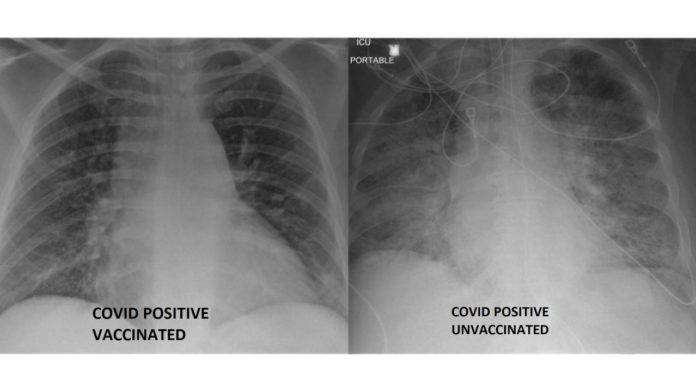

Dr. Jesse O’Shea, infektolog, ka publikuar imazhe me rreze X që tregojnë ndryshimin në mushkëritë e dy pacientëve të tij. Njëri u vaksinua kundër COVID-19, derisa tjetri nuk e mori vaksinën. Dallimi është befasues.

“Fotografia e parë është e një burri 47-vjeçar i cili mori vaksinën Pfizer dhe zhvilloi COVID-19, dy javë më vonë. Ai është mbipeshë, por pa ndonjë komorbiditet të njohur. Ai kishte rrjedhje hundësh, me dhimbje të lehta trupore dhe kollë të lehtë. Imazhi i mushkërive është relativisht normal. Fotografia e dytë është e pacientit 50-vjeçar pa obezitet, i cili nuk merr ilaçe. Skanimi i saj i mushkërive tregon mjegullim të përhapur, konsolidim në të dy mushkëritë me dëmtim dhe fashë që duket të jetë ndërlikimi më i keq i COVID -19 – sindroma e distresit akut respirator. “Kërkonte intubim, ventilim mekanik dhe oksigjenim të membranës ekstrakorporale, e cila është pjesa më e madhe e mbështetjes së jetës që ne mund të ofrojmë.”

Ai na rikujton se vaksinat janë efektive në parandalimin e sëmundjeve të rënda dhe vdekjeve, edhe në rastin e variantit delta të koronavirusit.